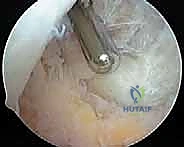

Arthroscopic photograph showing the resection of synovium in the notch.